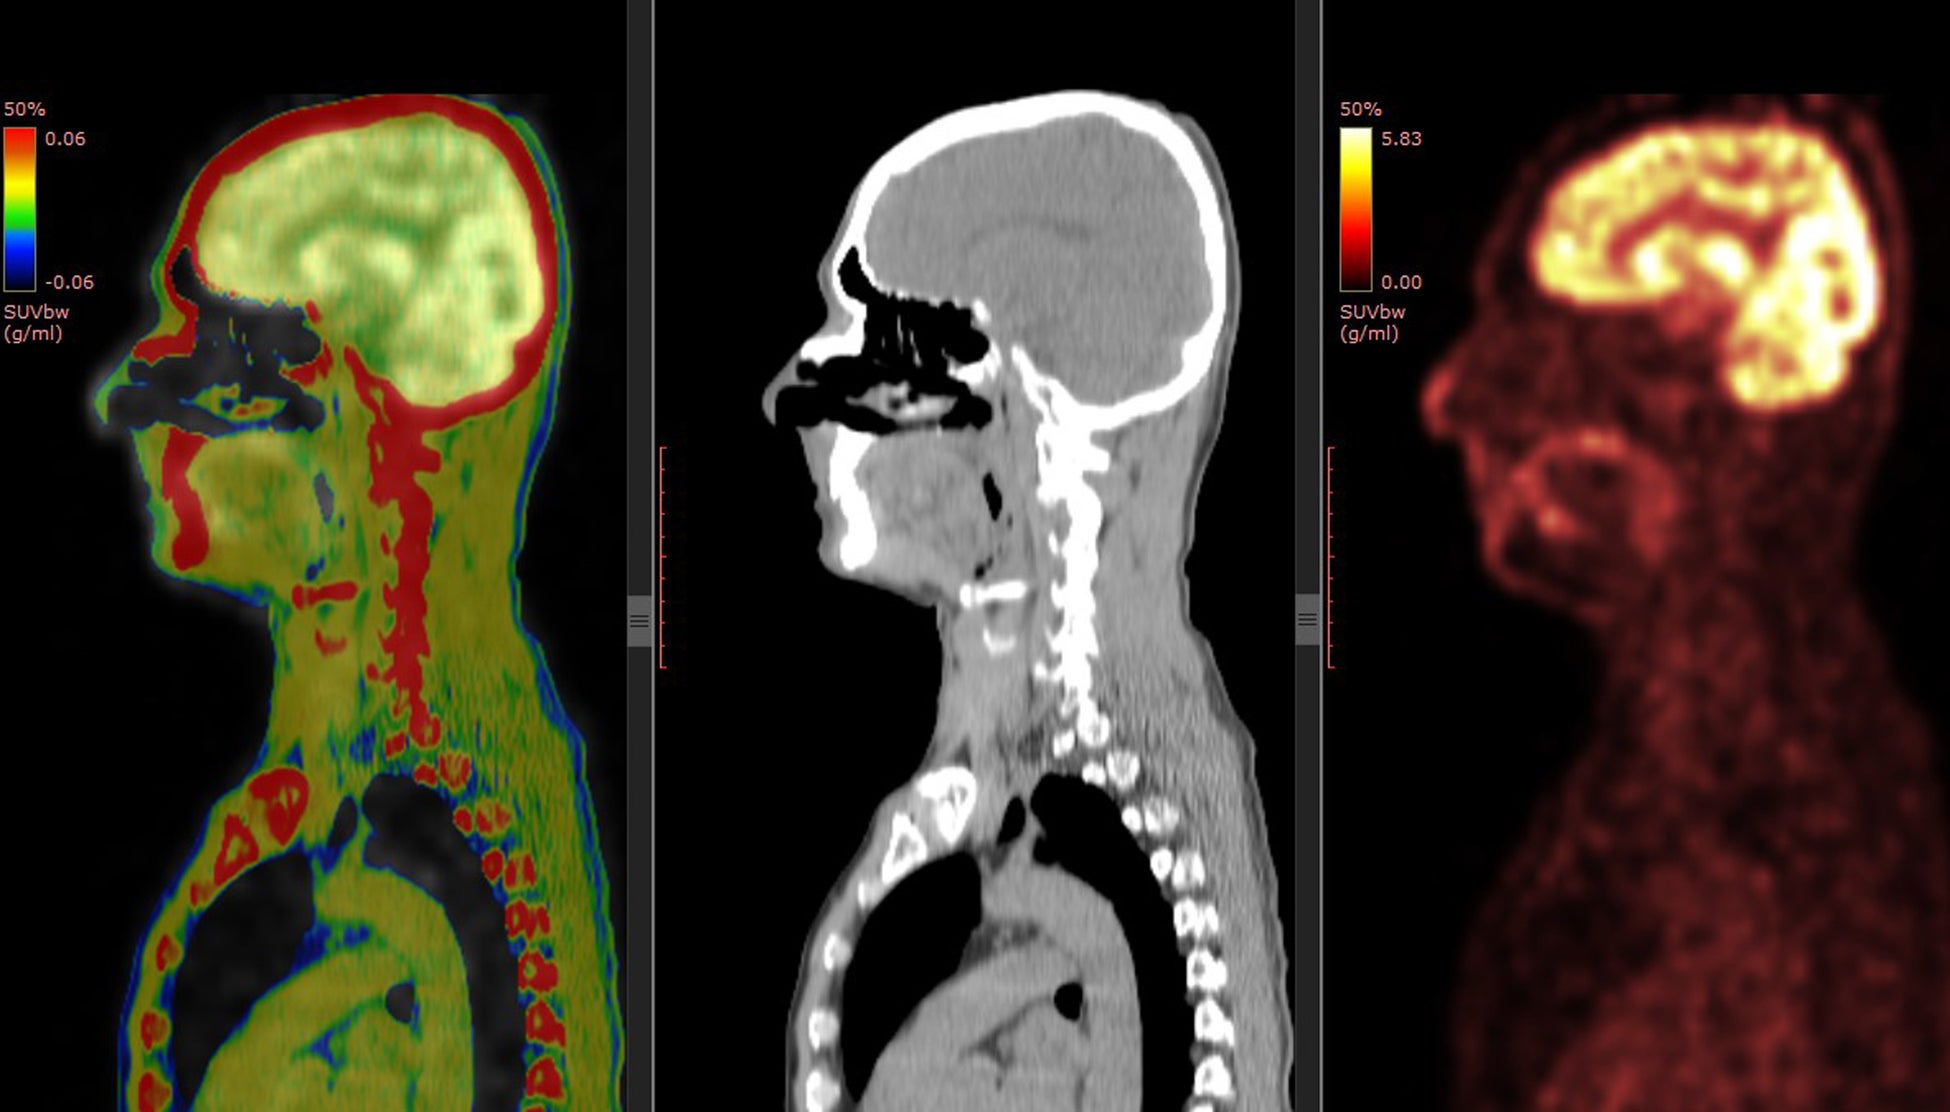

③画像だけでなく、動画での提供もできること

他社の遠隔画像システムの場合、診断結果はレポート(文字情報)とキー画像(送信画像のjpgなど)での提供と、せいぜい直交MPRが作成されるのみでした。「画像診断ラウンジ」はraw dataのまま送信可能で、キー画像も送信された画像だけでなく、動画(mp4など)、三次元画像(VR,MIPなど)、再構成画像(直交およびcurved MPR)などの提供もできるため、診断により役立てることができます。DICOM viewerはOsirixMD(Macのみ)を使用しており、多くのポストプロセス画像をキー画像として提供可能となっています。

④同時にCT,MRI,PET-CTなどを依頼すると料金が安くなる、診断精度が上がること

従来の遠隔画像診断の場合、同一患者の異なる検査では、読影医が異なる場合があり、結果に一貫性がないことも多く、料金も別々に請求され割高でした。「画像診断ラウンジ」では、CT,MRI,PET-CTなどを同時に依頼することで料金が加速度的に割安になります。それぞれの画像を参照して総合的に診断するので、診断精度の向上にも繋がります。